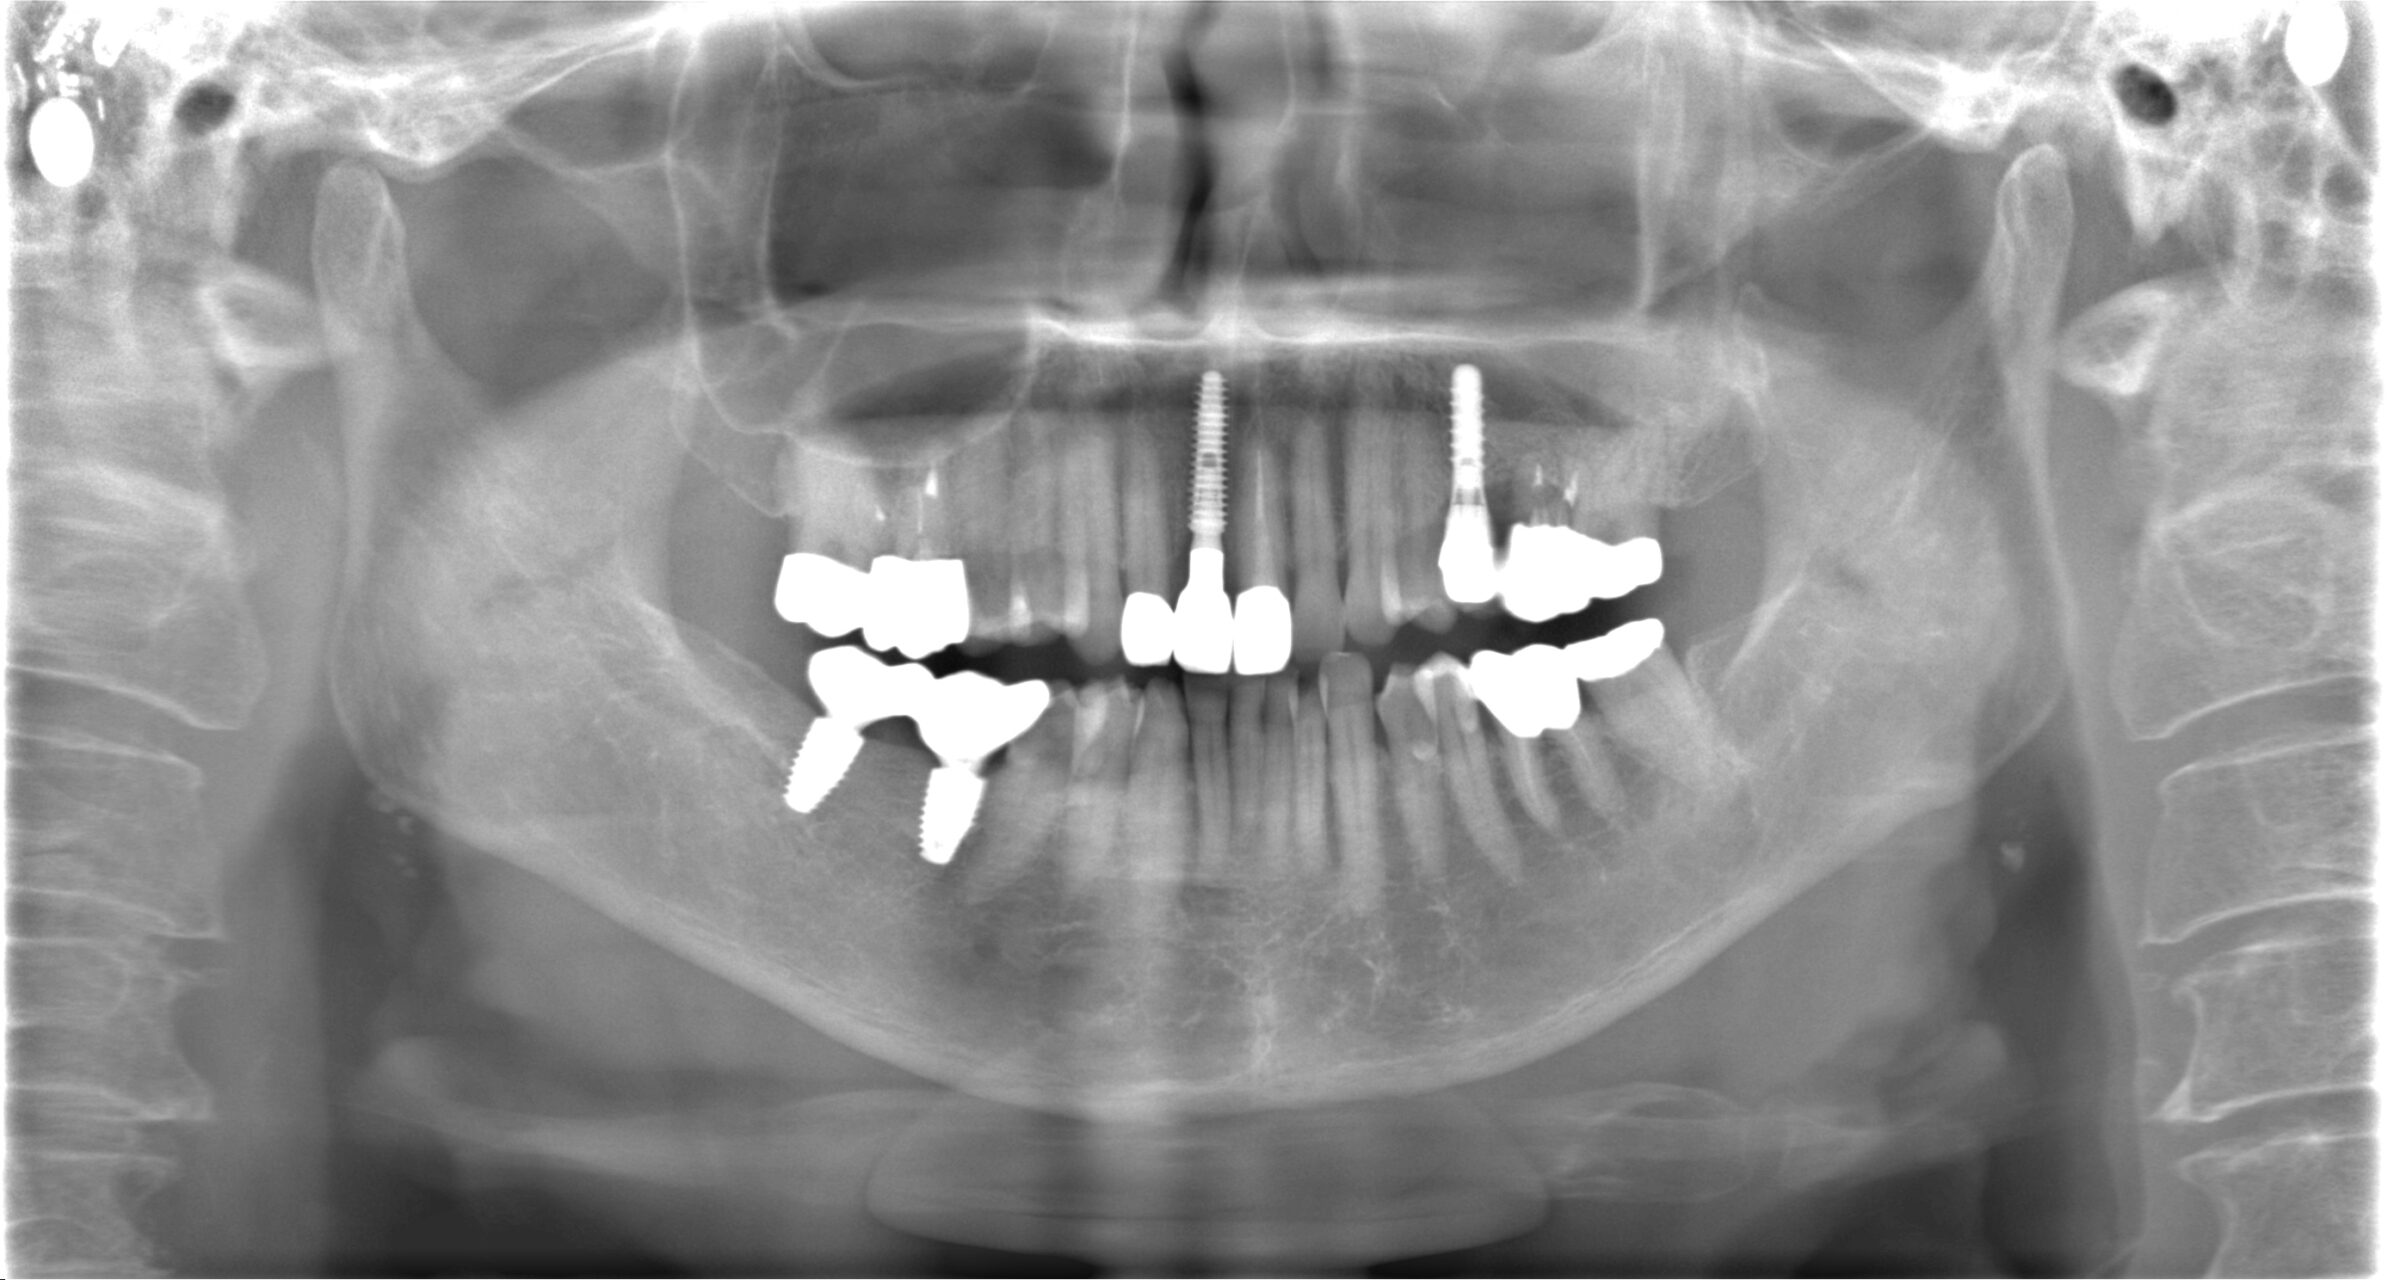

初診時のレントゲン写真

このように、前歯の欠損部にブリッジもしくは入れ歯を他院さんで提案されてしまい、当院にご相談に来られる患者様が多数いらっしゃいます。

今回の症例でも、右下のCT画像を見て頂くと分かるように、インプラントの外側(唇側)の骨がペラペラで薄いことが分かります。

シミュレーションと同じ位置にインプラントが埋め込まれていることが分かります。

治療後のレントゲン写真

精密に施術されたインプラントは20年30年とトラブルなくお使い頂けます。